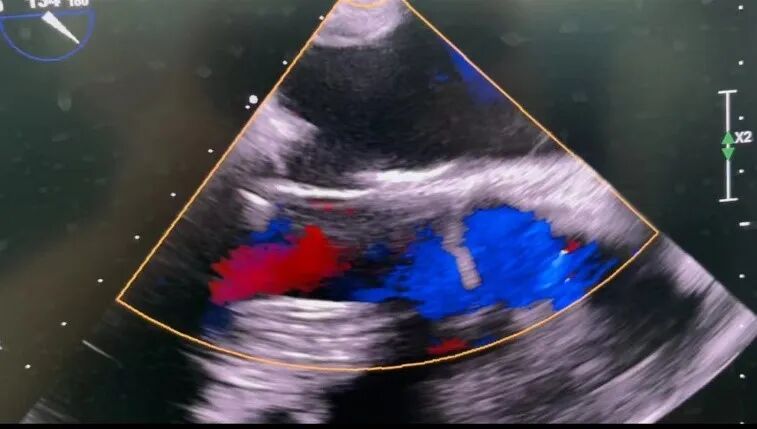

今日最后一台手术直播,也是本届CMC Week 2022云上手术直播的最后一台压轴手术是由武汉大学中南医院刘金平主任主刀的微创二建瓣成形+房颤射频消融+左心耳缝闭术。患者为65岁老年女性,心超提示:二尖瓣后叶脱垂(P1区、交界处)并重度关闭不全,LA 53mm、LV 56mm,EF 64%,二尖瓣瓣环径4.8cm。ECG:房颤律。拟首选二尖瓣成形,备二尖瓣生物瓣置换术,术中房颤射频消融。

手术经股动静脉插管建立体外循环,右侧4肋间腋前线6cm切口进胸,5肋间腋中线1cm切口置入胸腔镜,链式阻断钳以及升主动脉灌注管。术中游离上下腔静脉,充分显露左房顶和底部,经房间沟切口配合美敦力单、双极消融笔行左房Box隔离左右肺静脉。左房内拉出左心耳双极消融其根部,还纳后连接左上肺及左心耳消融线,单双极消融二尖瓣峡部线,5-0prolene线缝闭左心耳。术中探查二尖瓣后叶P1、P2脱垂,P2区腱索断裂,于P2区植入人工腱索,间断缝合植入30# Edward全环,注水评估形态及对合面积可,开放升主动脉后纵行切口右心房,单双极笔行右房射频消融术。术毕TEE提示二尖瓣P1区仍有少到中量许返流,遂重新阻断升主动脉于P1、P2交界区再置入人工腱索一根。开放后于右室流出道表面置入临时起搏导线,停机后TEE提示二尖瓣无反流,舒张期血流通畅,压差<2mmHg,左室流出道血流通畅,心电图呈窦性心律。

作为本届CMC Week 2022云上手术直播的压轴手术,刘金平主任通过以右侧第四肋间微创切口,不仅成功修复二尖瓣反流,还完成了房颤射频消融。手术过程流畅,以对患者最小的创伤,争取了最大的获益。充分展现了手术团队的精湛技术与默契配合。同时刘金平主任还在手术期间与嘉宾及观众对同期瓣膜与消融手术、双瓣置换手术的入路选择,视野暴露等相关问题进行了经验交流,让观众获益匪浅。